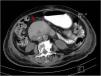

Se consultó al servicio de medicina interna para evaluación adicional y se solicitó tomografía computarizada (TC) abdominal con contraste oral, la cual reportó la presencia de un hemobezoar en la segunda y tercera porción del duodeno que causaba obstrucción aguda del intestino delgado (fig. 2).

Un mes posterior al egreso se programó TC abdominal con contraste oral, observándose resolución de la obstrucción duodenal (fig. 3), por lo que se retiró la sonda de alimentación y se continuó con la vigilancia.